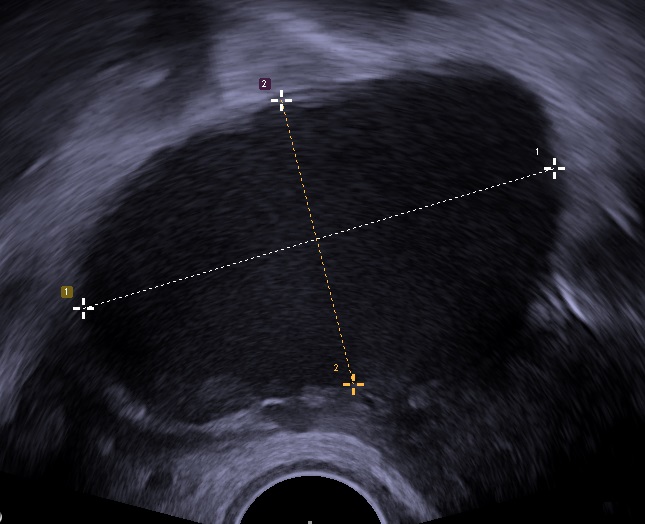

질식 초음파 검사로 촬영한 67 x 40 mm 크기의 자궁내막종으로, 다소 과립상의 내용물을 보입니다. - 난소에 생긴 자궁내막증으로 인한 것이다.